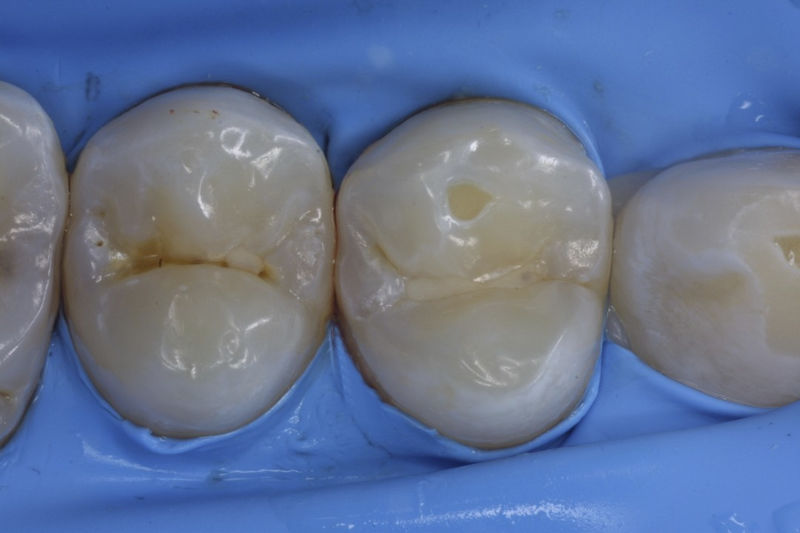

Son restauraciones con materiales plásticos color diente usados primariamente en dientes con caries pequeñas y puestas directamente en el diente.

Restauraciones fabricadas en el laboratorio con materiales estéticos, los cuales cubren de manera parcial dientes posteriores. Se utilizan primariamente para restaurar dientes con caries, fracturas y/o defectos amplios. Para poder enviar el caso al laboratorio se toman impresiones utilizando materiales de impresión o técnicas modernas digitales.

Disciplina fundamental de la Odontología enfocada en el diagnóstico, prevención y tratamiento restaurador de las piezas dentales que han sufrido daños. Su objetivo principal es devolver al diente su equilibrio biológico, funcional y estético cuando su integridad ha sido alterada. Resinas directas, incrustaciones, coronas.